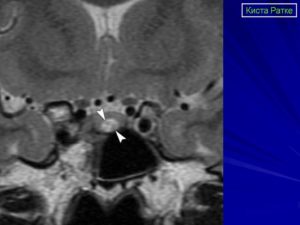

При визуализации киста кармана Ратке представляет хорошо отграниченное, срединно расположенное, не усиливающиеся образование между передней и промежуточной долями гипофиза. 40% кист имеет интраселлярную локализацию, 60% — имеют супраселлярный компонент. Чисто супраселлярная локализация встречается редко.

Магнитно-резонансная томография

Кисты кармана Ратке почти всегда имеют гомогенную интенсивность МР сигнала, в то время как кистозные краниофарингеомы и аденомы с кровоизлиянием имеют гетерогенный сигнал. [9] Уровни жидкости подразумевают кровоизиляние в анамнезе. Хотя кисты кармана Ратке не имеют характерных только для данной нозологии МР признаков. Большинство кист можно отнести к двум группам:

- Кисты кармана Ратке с низкой интенсивностью МР сигнала на Т1 взвешенных изображениях и высокой интенсивностью сигнала на Т2 взвешенных изображениях,

- Кисты кармана Ратке с высокой интенсивностью МР сигнала на Т1 взвешенных изображениях и различной интенсивностью МР сигнала на Т2 взвешенных изображениях

В первой группе содержимое кисты серозное и имеет сигнальные характеристики соответствующие ЦСЖ. Во второй группе содержимое кист богато мукополисахаридами, которые считаются продуктами муцин-продуцирующих клеток в стенке кисты.

В редких случаях повышенный сигнал на Т1 взвешенных изображениях сочетается с низким МР сигналом на Т2 взвешенных изображениях за счет комбинации факторов включающих наличие мукополисахаридов, продуктов распада гемоглобина, высокого содержания холестерола и сушенных клеточных масс.

Сигнальные характеристики в соответствии с содержимым кисты:

- T1

- 50% гиперинтенсивные (высокое содержание мукополисахаридов)

- 50% гипоинтенсивные

- T2

- 70% гиперинтенсивные

- 30% изо- и гипоинтенсивные

- T1 C+

- отсутствие контрастного усиления

- может присутствовать тонкое кольцевидное усиление прилежащей ткани гипофиза за счет сдавления [3,4]

- может присутствовать тонкое кольцевидное усиление отражающее метаплазию эпителия